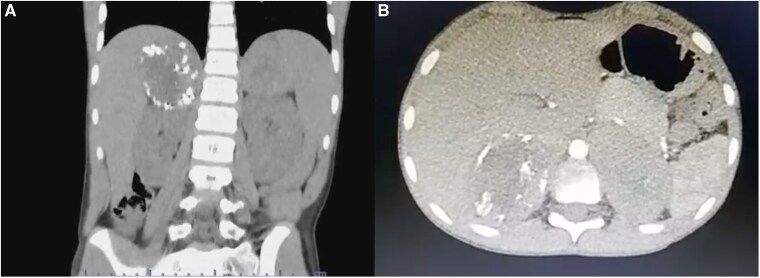

Adrenal leiomyomas are rare, benign tumors originating in the adrenal glands. They have a varied age of presentation, occur with a slight female predominance, and are typically unilateral, although bilateral cases can occur. Symptoms typically include abdominal or flank pain. This report presents a rare case of an 11-year-old male with disseminated molluscum contagiosum, diagnosed with bilateral adrenal leiomyomas. Imaging revealed large, heterogeneous adrenal masses, and the patient underwent successful adrenalectomy. This case underscores the rarity of adrenal leiomyomas in the pediatric population and highlights the critical role of imaging and surgical intervention in their management.